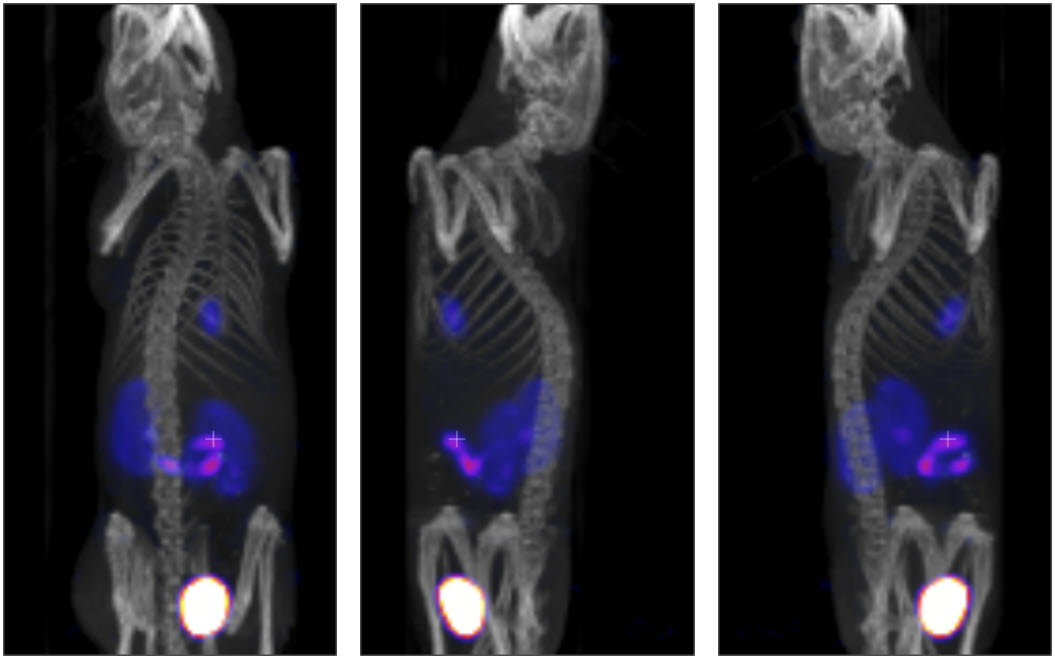

Example MIP projections at three different angles are shown below: